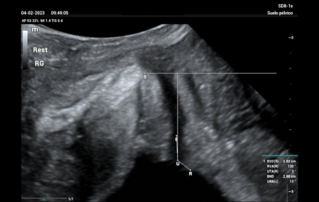

Female pelvic floor anatomy, which developed since the early 20th century, has had a variety of theories, including integral theory, three levels of vaginal support theory, "hammock hypothesis", and three-chamber system. Supporting structures such as pelvic floor muscles, fascia and ligament play an important role in maintaining the normal function of pelvic floor, among which levator ani muscle group is one of the most important supporting structures.